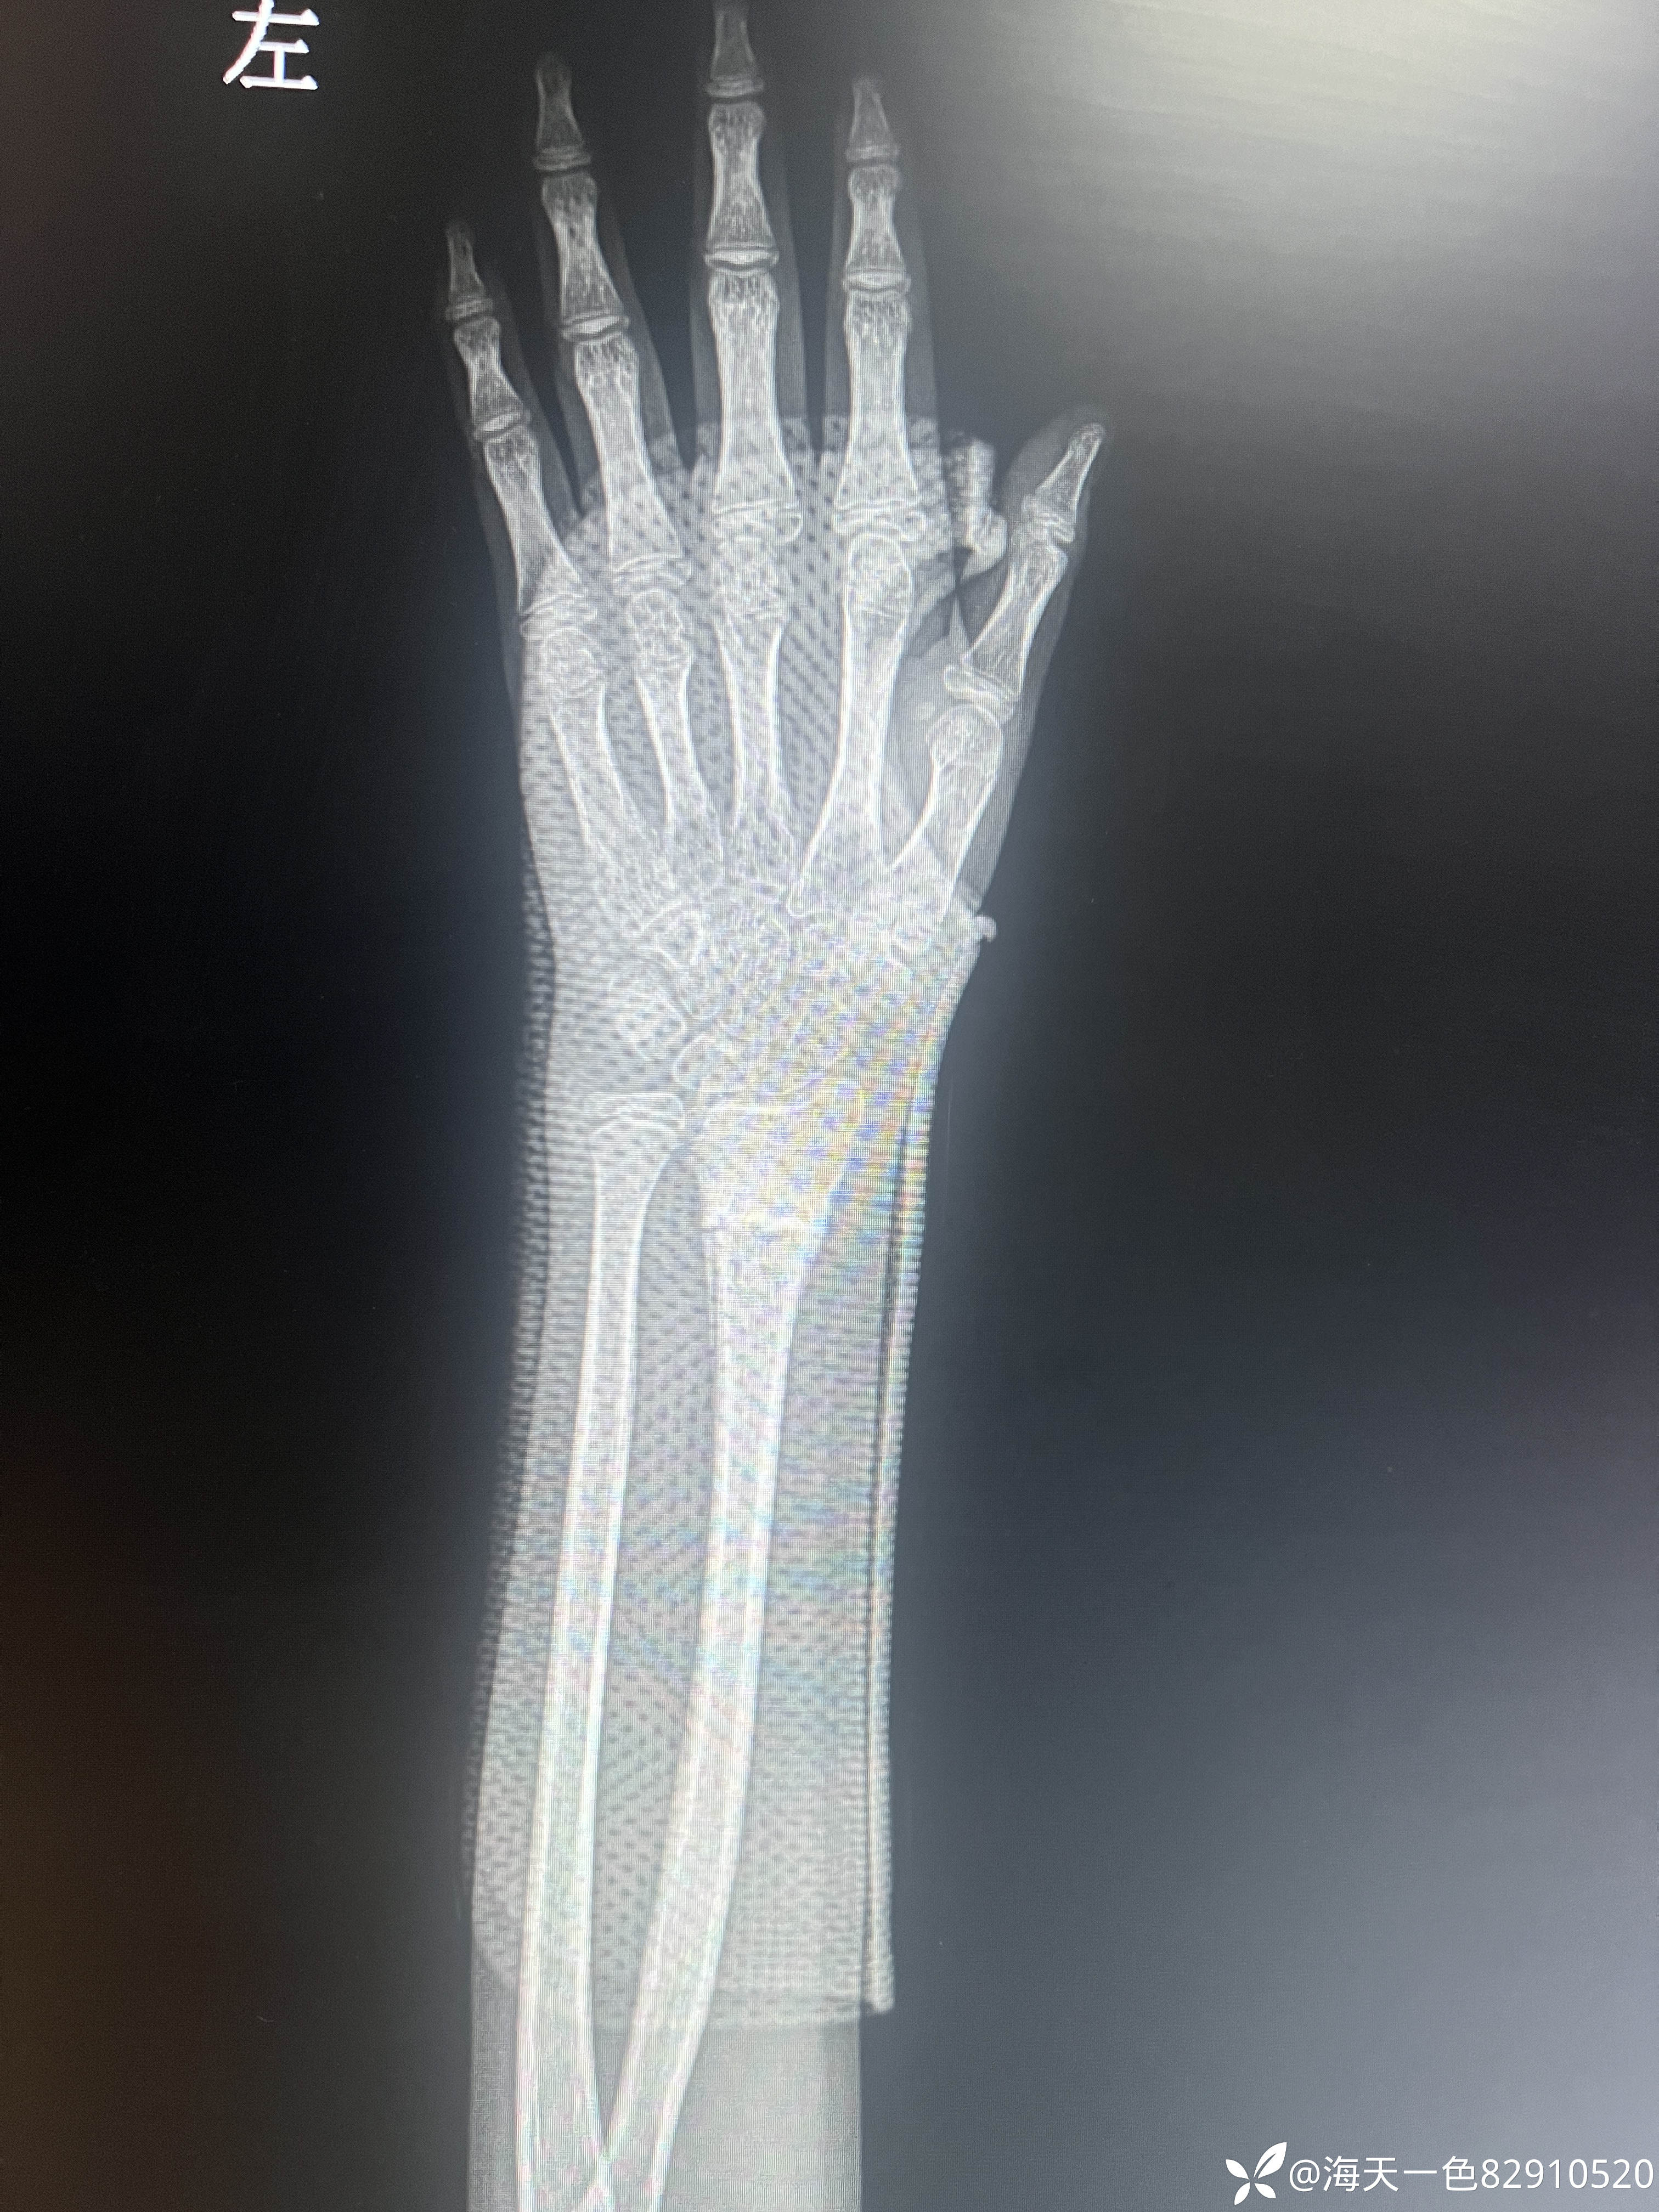

桡骨远端骨折

【患者信息】:患儿男性,14岁,

【主诉】:跑跳时不慎摔伤左腕关节肿痛14天

【临床诊断】:左桡骨远端骨折

【治疗经过及结果】:建议手术手术治疗,患儿家属未手术治疗,外院进行手法复位,复位拍片如下

移位角度有些大,预后影响大吗?